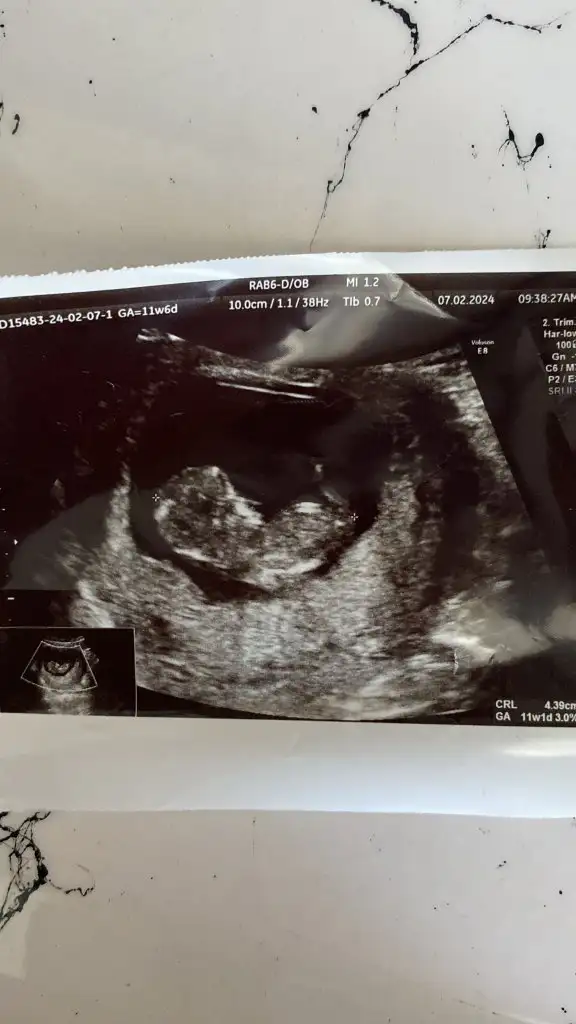

Canım bana da bakar mısın 11+1Kafası ne tsrafta anlasam söylerim de anlayamadım

İşte net görsem söylerim bakın bu arkadaşta bebek net görünüyor mesela.Diğer sefer gittiğimde kafası bilgisiyarda sağ taraftaydi şu gönderdigim fotoğraf varya belli olan o pozisyon onun diğer tarafa dönmüştü

Sizin bence erkek ama ben doktor değilim sadece kendi tecrübelerime dayanarak söylüyorum.Canım bana da bakar mısın 11+1